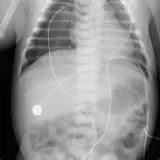

Over 2,100 interactive radiology cases, curated by radiologists for your level of training. Scroll, window, and view cases full screen — just like on PACS. Click linked findings in each writeup to jump straight to them on the image. Cases include sample reports, a focused discussion section, original illustrations, and videos.

Casos totalmente interactivos con las herramientas que esperaría de un PACS: scroll, ventana, zoom, pan, mediciones, ROI y modo de pantalla completa.

• Anotaciones enlazadas

Anotaciones extensas resaltan los hallazgos clave directamente sobre los casos. Haga clic en los hallazgos enlazados dentro de la descripción del caso para saltar a su ubicación exacta en el estudio.

Casos Interactivos

Desplace, arrastre, ajuste ventana y amplíe como en una estación PACS de trabajo

Aprenda con eficiencia gracias a hallazgos de imagen anotados e ilustraciones